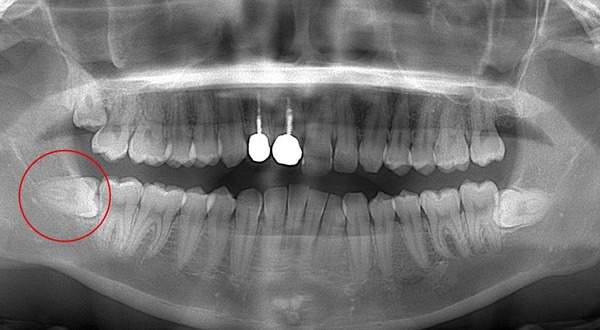

麻布十番歯科で親知らずが横向きに生えている症例のレントゲン写真のイメージ

親知らずを抜くのに痛みを伴いやすいものが写真とレントゲンにあるような真横にはえているもの、もしくは斜め下にはえている下顎の親知らずです。また、根が曲がっていたり、数が多いほど抜くのが難しい経口にあります。

この場合、歯ぐきを切ったり、歯を囲っている周りの骨を削って抜いていかなければなりません。

そのため、抜歯後は腫れや痛みが伴いやすくなります。 抜歯中は麻酔を行いますが、骨が硬い方は麻酔がなかなか効かないこともあります。そのため痛みを伴うことがあります。